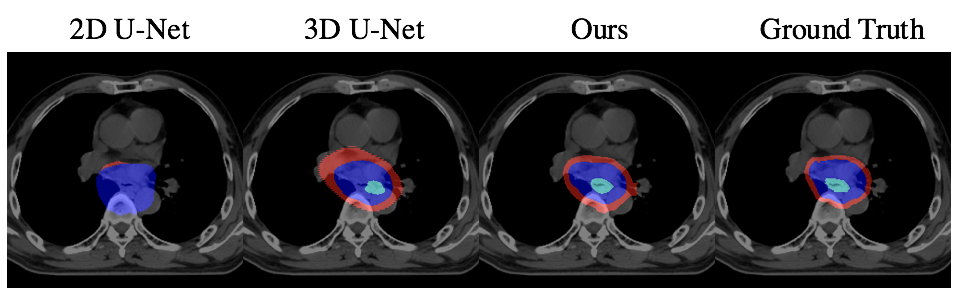

To evaluate our method, we chose the most commonly used CNN-based segmentation frameworks: 2D U-Net[8] and 3D U-Net[4] as our baselines. Since we focus on predicting the accurate radiotherapy target contouring, we trained and tested with valid slices that contain tumors. That is, given the volume where oncologists want to deliver radiation, we are able to segment the GTV, CTV and PTV regions precisely. For quantitative comparison, following metrics in [5], we use DSC, Sensitivity, and Specificity and ran with five-fold cross-validation. Table. 1 and Figure. 2 shows that our non-interactive method outperforms all the baselines both qualitatively and quantitatively. In the interactive setting, the results are evaluated on the selected sequences with “min median DSC” of GTV for each patient, in the exclusion of the slice we have reconstructed the features. As shown in Table. 2, the results are further improved after the interaction.